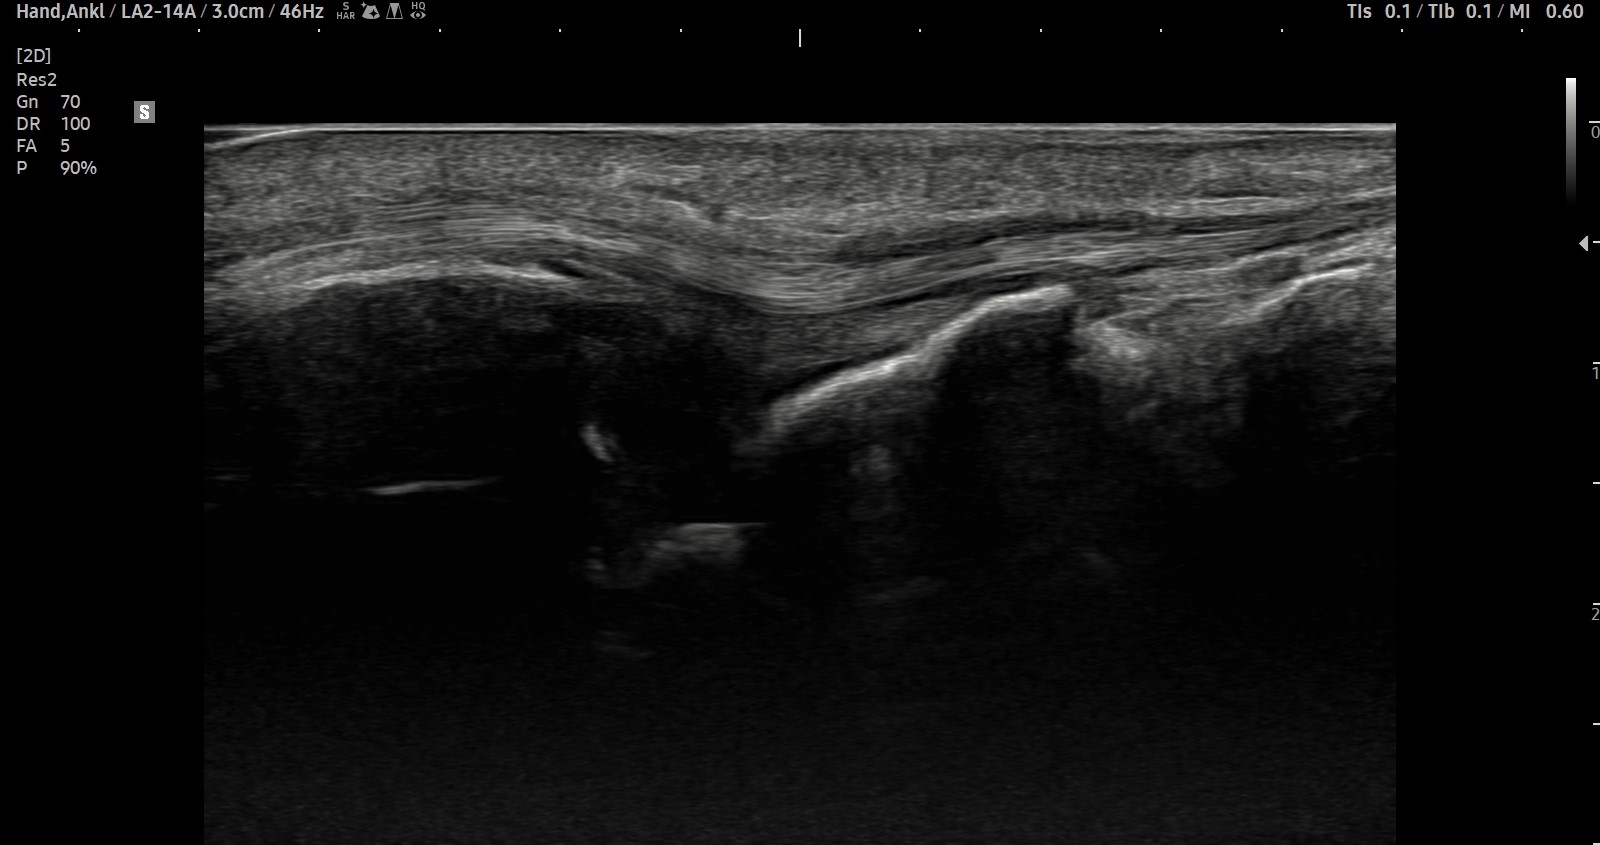

- 치료기간 : 25 .5 30 . ~ 25 . 6 .27

- 치료횟수 : 5 회(dna 1cycle)

양 손목 신근지대 건초염 & 건염

치료 전

치료 후